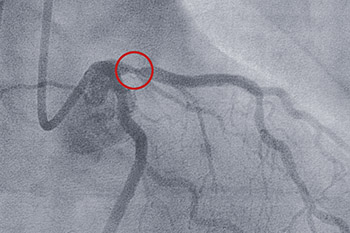

cardiac stent

• Balloon angioplasty clears blockages in arteries to restore blood flow to the heart or extremities. This is also called percutaneous transluminal coronary angioplasty (PTCA). Often, stents are inserted to support the tubular structure of the blood vessel and keep it open.

• Diagnostic cardiac catheterization diagnoses blockages and narrowing in arteries, evaluate the pumping ability of the heart, the functioning of heart valves, and to measure pressures within the heart.